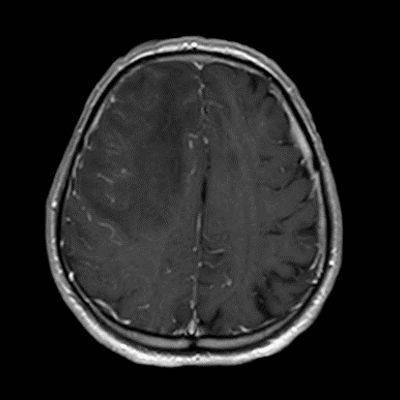

77 Y, E

1 aydır sol kol ve bacakta güçsüzlük, konfüzyon

Enfeksiyon markerları negatif

Serebral Amiloid Anjiyopatiye ile ilişkili inflamasyon (CAA-ri)

Serebral amiloid anjiopati ilişkili inflamasyon